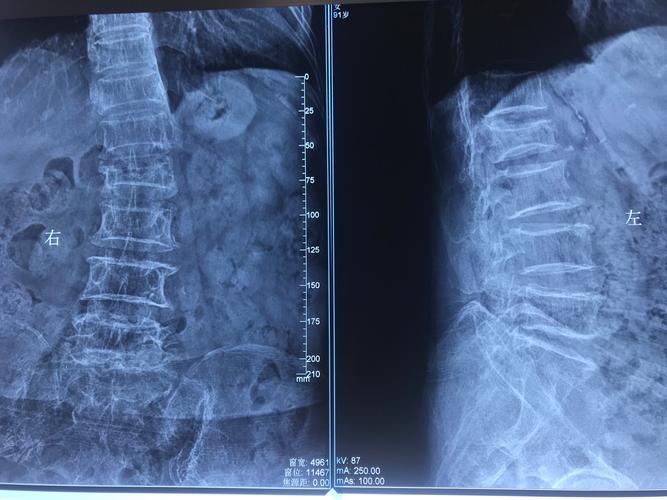

腰椎疼痛三天今天去医院拍片检查,结果为腰椎弯曲,椎体轻度骨质增生

您好,本人由于健身两年,最近感觉腰椎不舒服,随即去协和医院拍